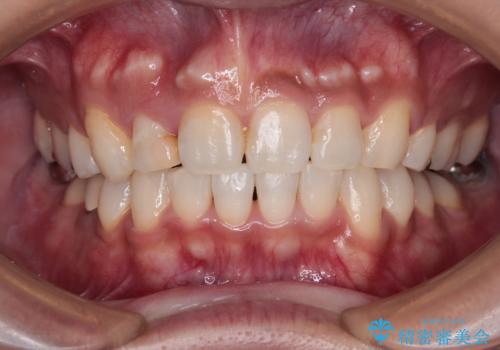

数十年に及んだ歯の変色が改善されたため、大変満足していただきました。